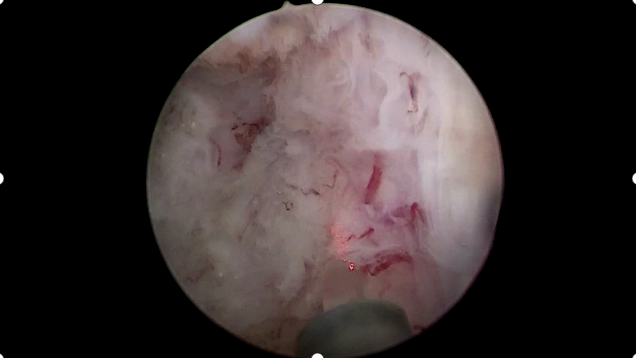

前列腺恶性肿瘤 是男性常见的泌尿系统肿瘤之一 当病情步入中晚期 治疗的关键在于结合系统治疗 一项能够直击病灶 持续作用的微创技术 为综合治疗拓展了新的可能 近日,贵州航天医院泌尿外科团队成功开展一例超声引导下经会阴前列腺碘125粒子植入术,为患者制定了个体化治疗方案。 案例分享 近期,一位年近八旬的男性患者因左侧髋部不适伴下肢放射痛前来就诊,初步检查提示可能存在前列腺肿瘤伴骨转移,为进一步明确诊断,患者随即转入泌尿外科诊治。泌尿外科为患者完善了相关检查,随后在超声引导下实施了经会阴前列腺穿刺活检,结合磁共振(MRI)影像与病理结果,最终明确诊断为前列腺腺癌(T4N0M1)。 考虑到患者年纪较大、身体状况比较弱,加上肿瘤已是晚期,已不适合创伤较大的前列腺癌根治性切除手术。为提供更佳的治疗方案,泌尿外科组织呼吸与危重症医学科肿瘤病区的专家进行了多学科讨论评估,征得家属同意后,定了一个分两步走的治疗方案:先实施前列腺肿瘤碘125粒子植入微创手术(把带辐射的小粒子放到患处杀灭肿瘤细胞),手术后,再配合药物(内分泌治疗)来控制病情。手术过程顺利,患者恢复良好,目前已出院并定期随访中。 术后植入粒子影像 我院多学科诊疗(MDT)已成为应对复杂疾病的常规模式,通过整合多学科的资源与优势,汇聚外科、内科、肿瘤、微创介入、影像、检验等多学科专家进行会诊,突出个体化治疗和综合全面治疗,提高诊疗效率和精准性,避免患者在多个科室间反复挂号奔波,缩短诊疗等待时间,让广大肿瘤、疑难重症患者享受到更加优质、专业、“一站式”的诊疗服务。 什么是放射性粒子植入技术 放射治疗是肿瘤治疗的常见手段之一,主要包括外照射与近距离放射治疗,碘125粒子植入属于持续低剂量率近距离放疗的一种,将微型放射性粒子永久植入前列腺组织内,通过持续释放射线作用于肿瘤区域,治疗前需通过影像学检查精确评估前列腺形态、体积,并制定个体化的剂量分布计划,术中在超声实时引导下植入粒子,以便根据实际情况调整进针路径与剂量分布,尽量使射线覆盖前列腺及其周边一定范围。该技术通常适用于部分局部进展性或转移性前列腺肿瘤患者,可作为综合治疗策略中的一环。 放射性粒子植入技术优势 1.能够把粒子准确植入肿瘤中,定位精准,靶向性强,高度适形。 2.肿瘤接受的放射剂量明显增加,而不增加正常组织的剂量。 3.持续低剂量率放射,能对不同分裂周期的肿瘤细胞进行不间断照射,提高了放射敏感性,累计射线剂量可达外放疗的2~3倍,有较高的放射生物效应。 4.粒子植入的部位肿瘤组织可被杀灭,距粒子1cm以外的正常组织几乎不受损伤,能有效降低正常组织受照剂量,正常组织损伤小,几乎不造成白细胞下降、骨髓抑制、胃肠道反应、脱发等副作用,病人无痛苦。 5.粒子外壳为钛合金,与人体有很好的组织相容性,不会产生排异及放射泄漏。 6.与其他的肿瘤治疗方法相比,创伤小、生活质量高、住院时间短。 7.能与手术、化疗及外放疗配合互补提高疗效。 注:本文仅为医疗技术介绍,具体治疗方案请务必咨询临床医生,并结合患者个体情况制定。部分图片来源于网络,如有侵权,请联系删除。 贵州航天医院 泌尿外科专家简介 石 英 泌尿外科党支部书记、主任,主任医师 中国医师协会泌尿外科分会感染协作组委员,奥林巴斯泌尿系软镜西南区专家组成员,西南地区第一批输尿管软镜专家组成员,贵州省医学会泌尿外科分会委员,贵州省性学会理事,贵州省性学会常务委员,贵州省泌尿外科专业医疗质量控制中心专家委员会委员。 从事泌尿外科专业近30年,熟练掌握泌尿系各类疾病的诊治,具有丰富的临床经验,擅长泌尿系结石、腹膜后肿瘤及泌尿系肿瘤的手术治疗,对泌尿系感染、泌尿系结核、尿源性脓毒血症的救治有独到的见解及抢救经验,在贵州省率先引入输尿管软镜技术,同时在男科领域,对男性阳痿、早泄及前列腺疾病有很深的研究。 李国成 泌尿外科副主任,副主任医师 中国人体健康科技促进会男科学专业委员会委员,贵州省性学会泌尿外科分会委员,贵州省医学会男科学分会委员,遵义市医学会男科学分会副主任委员兼秘书长,遵义市医学会泌尿外科分会常务委员,贵州航天医院男科带头人。 从事泌尿外科及男科工作10余年,曾多次前往上海交通大学附属第一人民医院、中国中医科学院西苑医院进修学习男科;擅长性功能障碍的诊治、男性整形手术、前列腺增生激光手术、显微手术等。 李 凯 中共党员,泌尿外科副主任医师 贵州航天医院肿瘤腔镜组带头人,擅长肾癌根治术、输尿管癌根治术、膀胱及前列腺癌根治术、腹腔镜输尿管狭窄切除吻合术、输尿管切开取石术等手术,在遵义市率先开展泌尿系结核后膀胱挛缩全腹腔镜下膀胱扩大术。 贵州省医学会泌尿外科分会青年委员,遵义市医学会男科分会常务委员,遵义市医学会泌尿外科分会常务委员。 贵州航天医院泌尿外科简介 • ✦ 基本情况 ✦ • 贵州航天医院泌尿外科创建于20世纪60年代,经过几代人的努力,微创与内镜手术占比达90%以上,科室亚专业框架完善。是贵州省临床重点专科建设单位、北京清华长庚医院李建新教授团队诊疗及会诊中心、北京医学会尿路修复与重建诊疗及会诊中心、上海公济泌尿外科集团遵义中心、上海援黔专家李铮教授男科工作室、贵州省泌尿外科质量控制专家委员单位。 • ✦ 专科特色技术 ✦ • (一)泌尿系结石内镜碎石技术 泌尿系结石微创治疗领域方面是贵州省首家引进科医人钬激光碎石技术科室,在遵义地区率先掌握输尿管硬镜、软性镜,经皮肾镜钬激光碎石技术。目前是北京清华长庚医院泌尿外科“手把手”经皮肾镜碎石技术培训基地、贵州省输尿管软镜培训基地。 1.负压吸引可弯曲软镜鞘电子软镜碎石术 2.标准与超微通道相结合的经皮肾镜碎石取石术 (二)微创腹腔镜技术 泌尿外科腹腔镜技术师承于浙江省人民医院、北大、北京解放军总医院。目前采用经腹、经后腹双入路法的腹腔镜技术完成肾部分切除、肾切除、肾输尿管全长切除、肾盂输尿管成形、输尿管狭窄吻合、膀胱翻瓣等手术。在遵义地区率先掌握腹腔镜下膀胱癌根治术、腹腔镜下前列腺癌根治术。 (三)男科、盆底技术临床应用 遵义地区男科分会主委单位,是贵州省首家引进尿动力学检查并取得了全国资质认证科室,也是贵州省首家进行RigiScan检查的单位。在遵义地区率先掌握显微取精子技术以及显微镜下治疗精索静脉曲张、显微镜下输精管吻合、输精管附睾吻合技术。率先采用前列腺激光剜除术治疗前列腺增生症。在陆军军医大学西南医院泌尿外科主任沈文浩教授指导下,完成遵义市首例神经源性膀胱骶神经调节刺激器置入术。 • ✦ 诊疗范围 ✦ • 诊疗范围(除外肾移植、癌栓):泌尿系结石、泌尿系肿瘤、肾上腺疾病、肾积水、前列腺增生、男性生殖器功能障碍(精索静脉曲张、生殖道感染、输精管梗阻等)、盆底功能障碍性疾病(膀胱脱垂、排尿功能异常、尿失禁)、泌尿生殖系畸形。 泌尿外科拥有独立门诊治疗室、日间手术室、尿动力学检查室、精液分析检查室、男性勃起功能检查及治疗室、ESWL治疗室、结石分析检查室。